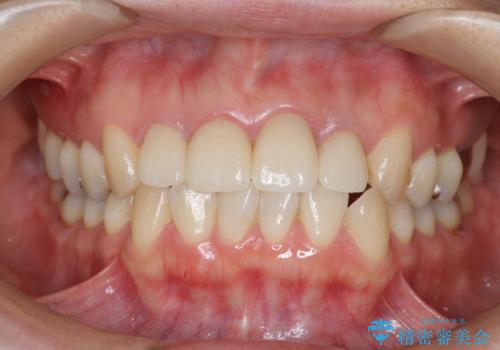

金属のフレームを用いるクラウンは色調が暗くなる傾向にありますが、セラミッククラウンに置き換えたことで自然な明るさ、審美性を取り戻すことができました。